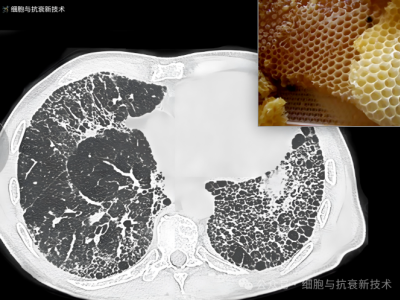

外泌體霧化可治療肺部結(jié)節(jié)及肺纖維化

2019年新冠疫情后,大家對肺部損傷比較關(guān)注,加之生活工作壓力以及檢測技術(shù)的進步,使結(jié)節(jié)成為體檢報告上出現(xiàn)的高頻詞匯,其中包括肺部結(jié)節(jié),結(jié)節(jié)的出現(xiàn)給部分人群增添了焦慮。外泌體作為先進治療藥品,是當(dāng)前生